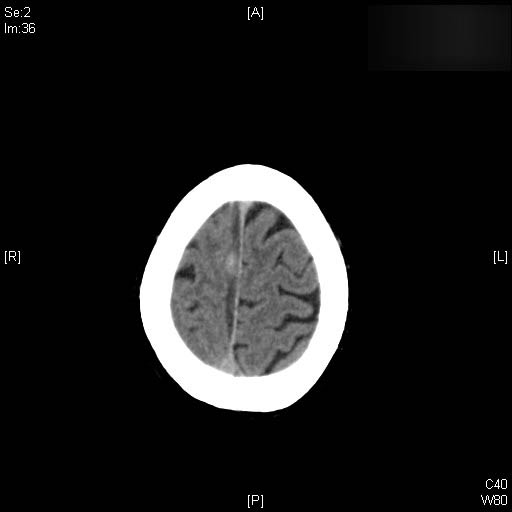

AVC amplio de territorio de A. cerebral media